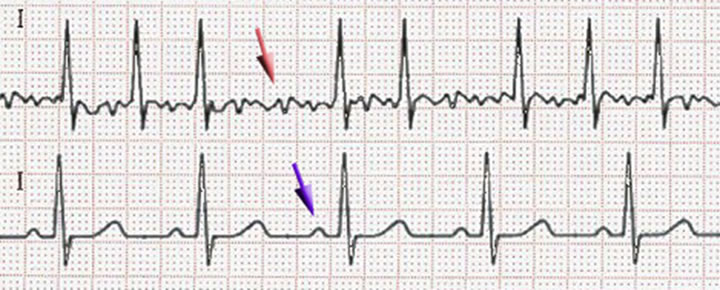

Ritmo normal abajo y fibrilación arriba mostrada en electrocardiograma.

Ritmo normal abajo y fibrilación arriba mostrada en electrocardiograma.

Se diagnostica a través de un electrocardiograma, se confirma con el Holter, con el ecocardiograma podemos analizar la parte estructural del corazón y ver si existen daños de forma directa o indirecta.

Indiscutiblemente la arritmia es tan obvia en ocasiones que el estetoscopio pude ser suficiente para hacer el diagnóstico presuncional, siempre deberá de corroborarse en la medida de lo posible.